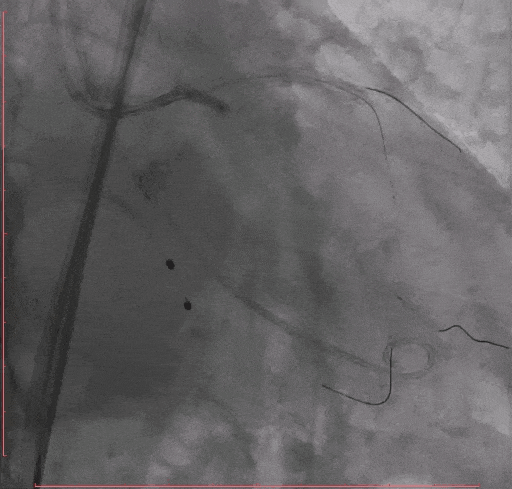

Step 8 Taurus 26 瓣膜释放后造影

Step 9. 患者出现心衰,血流动力学不稳,予以IABP植入

术后复查超声心动图:人工瓣膜功能正常,主动脉瓣峰值流速179m/s,平均压差7mmHg,未见瓣周漏。